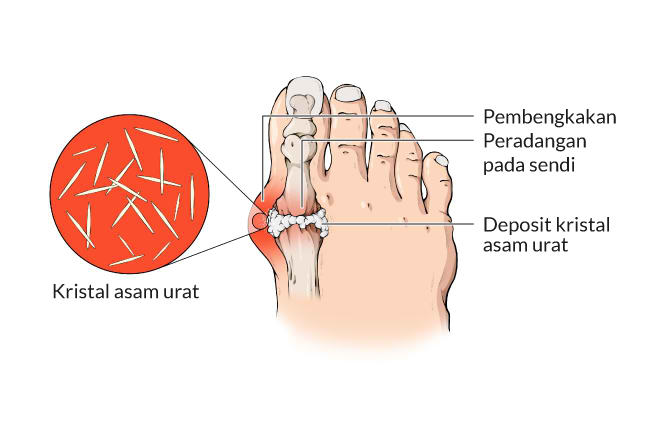

Asam Urat Penyebab Gejala Pemeriksaan Cara Pencegahan

Asam Urat Penyebab Gejala Pemeriksaan Cara Pencegahan

Asam Urat Penyebab Gejala Pemeriksaan Cara Pencegahan

Asam Urat Penyebab Gejala Pemeriksaan Cara Pencegahan